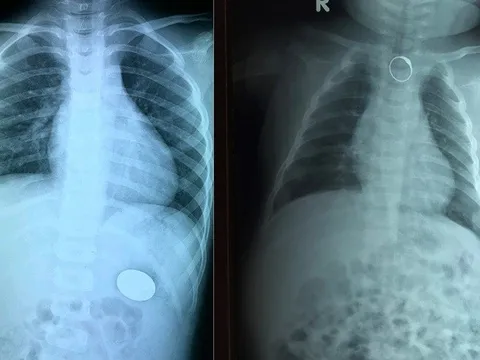

Cẩn trọng khi trẻ nuốt phải dị vật

2 trường hợp bệnh nhi 2 tháng tuổi và 4 tuổi vừa được các bác sĩ Bệnh viện Đa khoa Xuyên Á (TP. Hồ Chí Minh) nội soi gắp dị vật đường tiêu hoá là chiếc nhẫn và đồng xu.